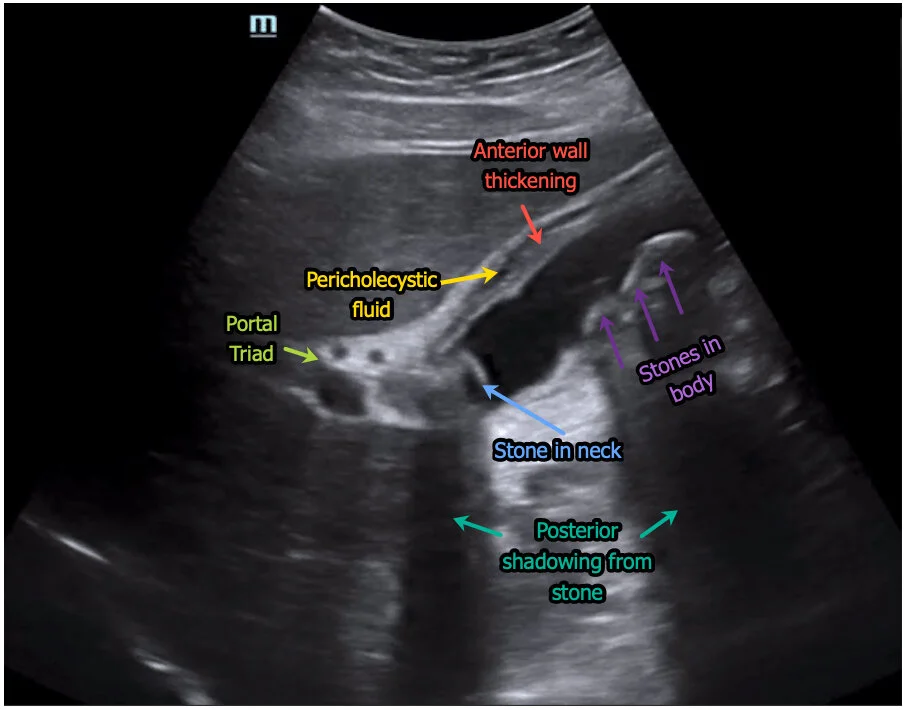

Biliary POCUS revealed the following:

Long axis view — multiple gallstones including one in the neck (not the hyperechoic rim with clearly defined posterior shadowing. Wall thickening with pericholecystic fluid seen. The patient also had positive Sonographic Murphy’s sign (though obviou…

Long axis view — multiple gallstones including one in the neck (not the hyperechoic rim with clearly defined posterior shadowing. Wall thickening with pericholecystic fluid seen. The patient also had positive Sonographic Murphy’s sign (though obviously not depicted here).

• Gallstones -- especially in the neck as this is where they're most problematic

• Wall thickening > 3mm (measure anterior wall)

• Pericholecystic fluid